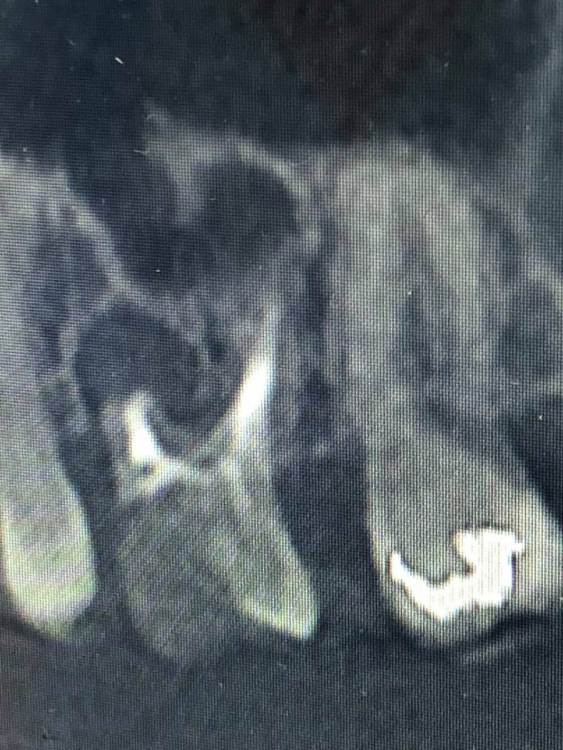

Здравствуйте ! Ситуация следующая - 6 сверху коронка с резекцией , долгое время осталась без антагониста , соотвественно выдвинулась (это уже мое предположение) . Чтобы спасти зуб , доктор принял решение повести гемисекцию корня . После - осталась рассечена десна .. Доктор говорит десна заживет , но визуал мягко говоря напрягает , так как при улыбке у меня это все видно ..

Фото 7,8 - Также была проведена резекция кисты 5 зуба снизу , с коронкой , и установка 7 импланта в качестве антагониста верхней 7 . Одной операцией . Коронка оголилась , швы сняли на 3 день .. доктор также утверждает что в дальнейшем будет все хорошо , зарастет . Также очень смешает внешний вид десны , десна стала волной даже на 6 ..